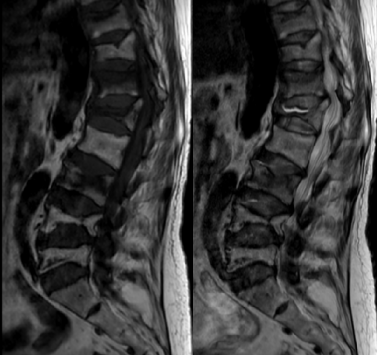

了解到优米app下载ios骨伤科不仅手法复位技术有绝招,微创手术也做得相当出色,她慕名前来,找到了张镇主任。张镇在详细了解谢某的病情后,为她制定了个性化治疗方案。首先保持卧床休息,以减少腰部和髋部的进一步损伤,并给予止痛药物以缓解疼痛;随后,进行了系列常规检查,以便全面掌握身体状况,同时,紧急进行了胸腰椎核磁共振检查,以确定椎体压缩的数量和程度。

检查结果显示,谢某的身体状况良好,但骨折情况却相当严重。除了右侧股骨颈骨折伴有错位外,还有胸10、胸12、腰1、腰3和腰5等5个椎体的新鲜骨折。面对如此严重的多发骨折,传统的手术方式显然不是最佳选择,因为就算是年轻人也难以承受长时间的手术和麻醉。针对这一特殊情况,张镇提出了分多次进行微创手术的方案。这样既可以减少手术对患者身体的负担,又能达到最佳手术治疗效果。